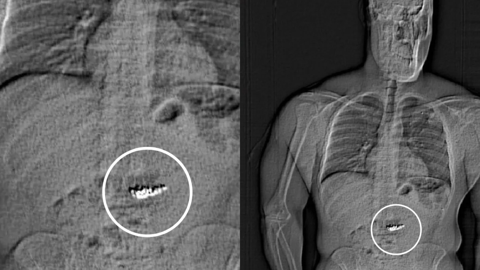

ABD’nin Florida eyaletinde yer alan Orlando’daki Millenia Alışveriş Merkezi’nde, lüks mücevher markası Tiffany & Co. mağazasında büyük bir soygun gerçekleşti. Olayın baş şüphelisi 32 yaşındaki Jaytan Gilder, toplam 769 bin 500 dolar (yaklaşık 28 milyon 200 bin lira) değerinde mücevher çaldı.